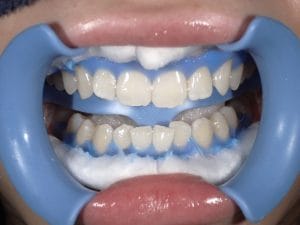

ホワイトニング

Case005 – ホワイトニングト

歯が欠けていて、隙間がある。

歯並びが気になる。

亀裂が入っている。

歯の無いところがある。

見える銀歯が気になる。

綺麗な口元になりたい。

という患者様の診療です。

上はジルコニアセラミックでかけているところを修復しながら、綺麗な歯並びで、患者様のお好きな白い歯に。

下の歯の無い所にはインプラント。

見える銀歯は外して綺麗な歯に修復。

また、ホワイトニングをして上の歯との色のギャップを少なくして、明るい口元にしました。